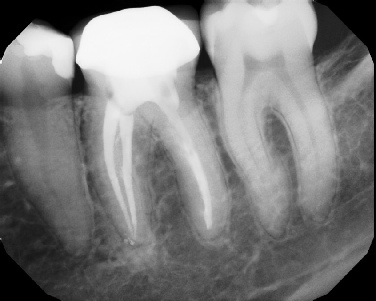

COMPLICATED ANATOMY LARGE LESIONS CALCIFIED CANALS PERFORATION / RESORPTION SEPARATED INSTRUMENTS SURGICAL CASES RETREATMENT / pOST REMOVAL OPEN APICES ACCESS THRU CROWNS Root Canal Case Portfolio

Pre-op Post-op 6 mos.